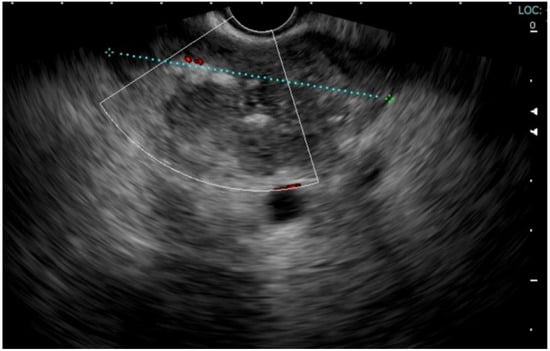

Approximately two months after the hospitalization, they returned to the hospital with epigastric pain and fever (38 °C). Laboratory results showed a WBC count of 14,530/mm3 (neutrophils: 78%) and a CRP level of 163 mg/L (<5 mg/L), procalcitonin 0.14 ng/mL. Pancreatic enzymes and liver function test results were within the normal ranges. An abdominal CT scan showed the presence of multiple confluent fluid collections extending from the head to the tail along the entire pancreatic profile containing air (Figure 1). An endoscopic investigation and an endoscopic ultrasound (EUS) were performed. The upper endoscopy revealed the presence of a fistula opening of about 8 mm in diameter in the duodenum bulb with leakage of purulent material (Figure 2). EUS showed the presence of air in the fistula and a complex 5 cm fluid collection in the tail of the pancreas (Figure 3). An abdominal CT scan with gastrografin confirmed the fistulous channel originating from the first duodenal portion, which gives rise to two branches, anteriorly in the head of the pancreas and posteriorly in the tail. After a collegial reunion with clinicians, surgeons, radiologists, and gastroenterologists, it was decided to proceed with the drainage of the larger pancreatic collection in an attempt to heal the fistula with the duodenum. EUS-guided trans gastric drainage of the fluid collection was performed using a 16 × 20 mm lumen-apposing metal stent (LAMS, Hot-Spaxus, Taewoong Medical Co., Gimpo, Korea), obtaining drainage of copious purulent material in the stomach (Figure 4).

Figure 3.

EUS showed the presence of air in the fistula and a complex 5 cm fluid collection in the tail of the pancreas.